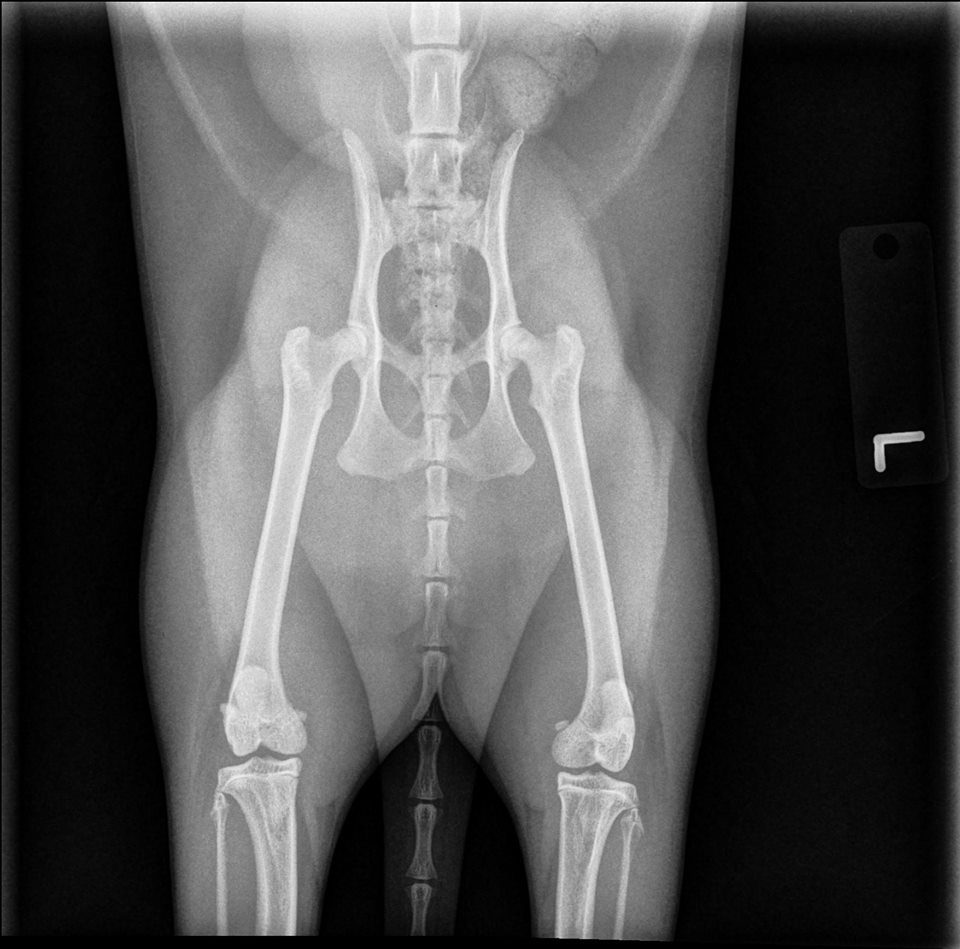

- Image interpretation is what we do all day long, and we are good at it!

- Significant findings are often overlooked because they are not recognized in the images. This is one of the primary reasons to use us!

- It is always a good idea to have at least two people (you and us) evaluate images in a team-based approach.

- Having all of your studies interpreted is taking the quality of medicine you practice to the next level.